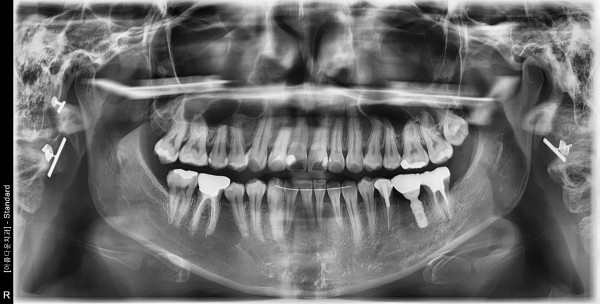

40대 여성 임플란트 식립